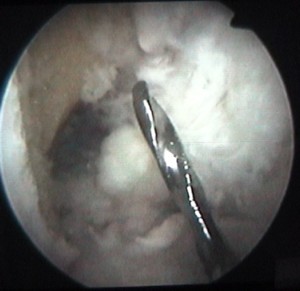

cette vis sert à attacher le ligament |

et elle est maintenant vissée à fond |